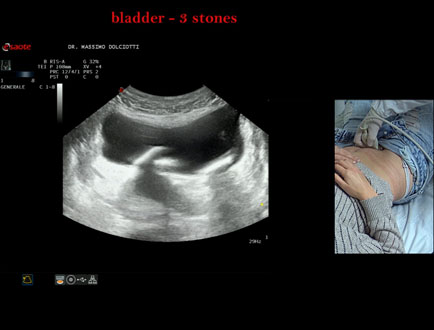

Data inserimento: 21/10/2025

Ecografia del: 15/10/2025

Strumento: Esaote MyLab Eight

Sonda: Convex Multifrequenza 1-8 MHz

Età Paziente: F 45 anni

Motivazione dell'esame: da alcuni mesi, disuria ed infezioni urinarie recidivanti.

Commento all'esame: le immagini ed il video documentano 3 immagini iperecogene, con cono d'ombra posteriore, da ricondurre a litiasi multipla della vescica.

Conclusioni: 3 calcoli della vescica (3 bladder stones).

Presentazione: Dr. Massimo Dolciotti - Ancona

Elaborazione digitale: Andrea Dini - Ancona